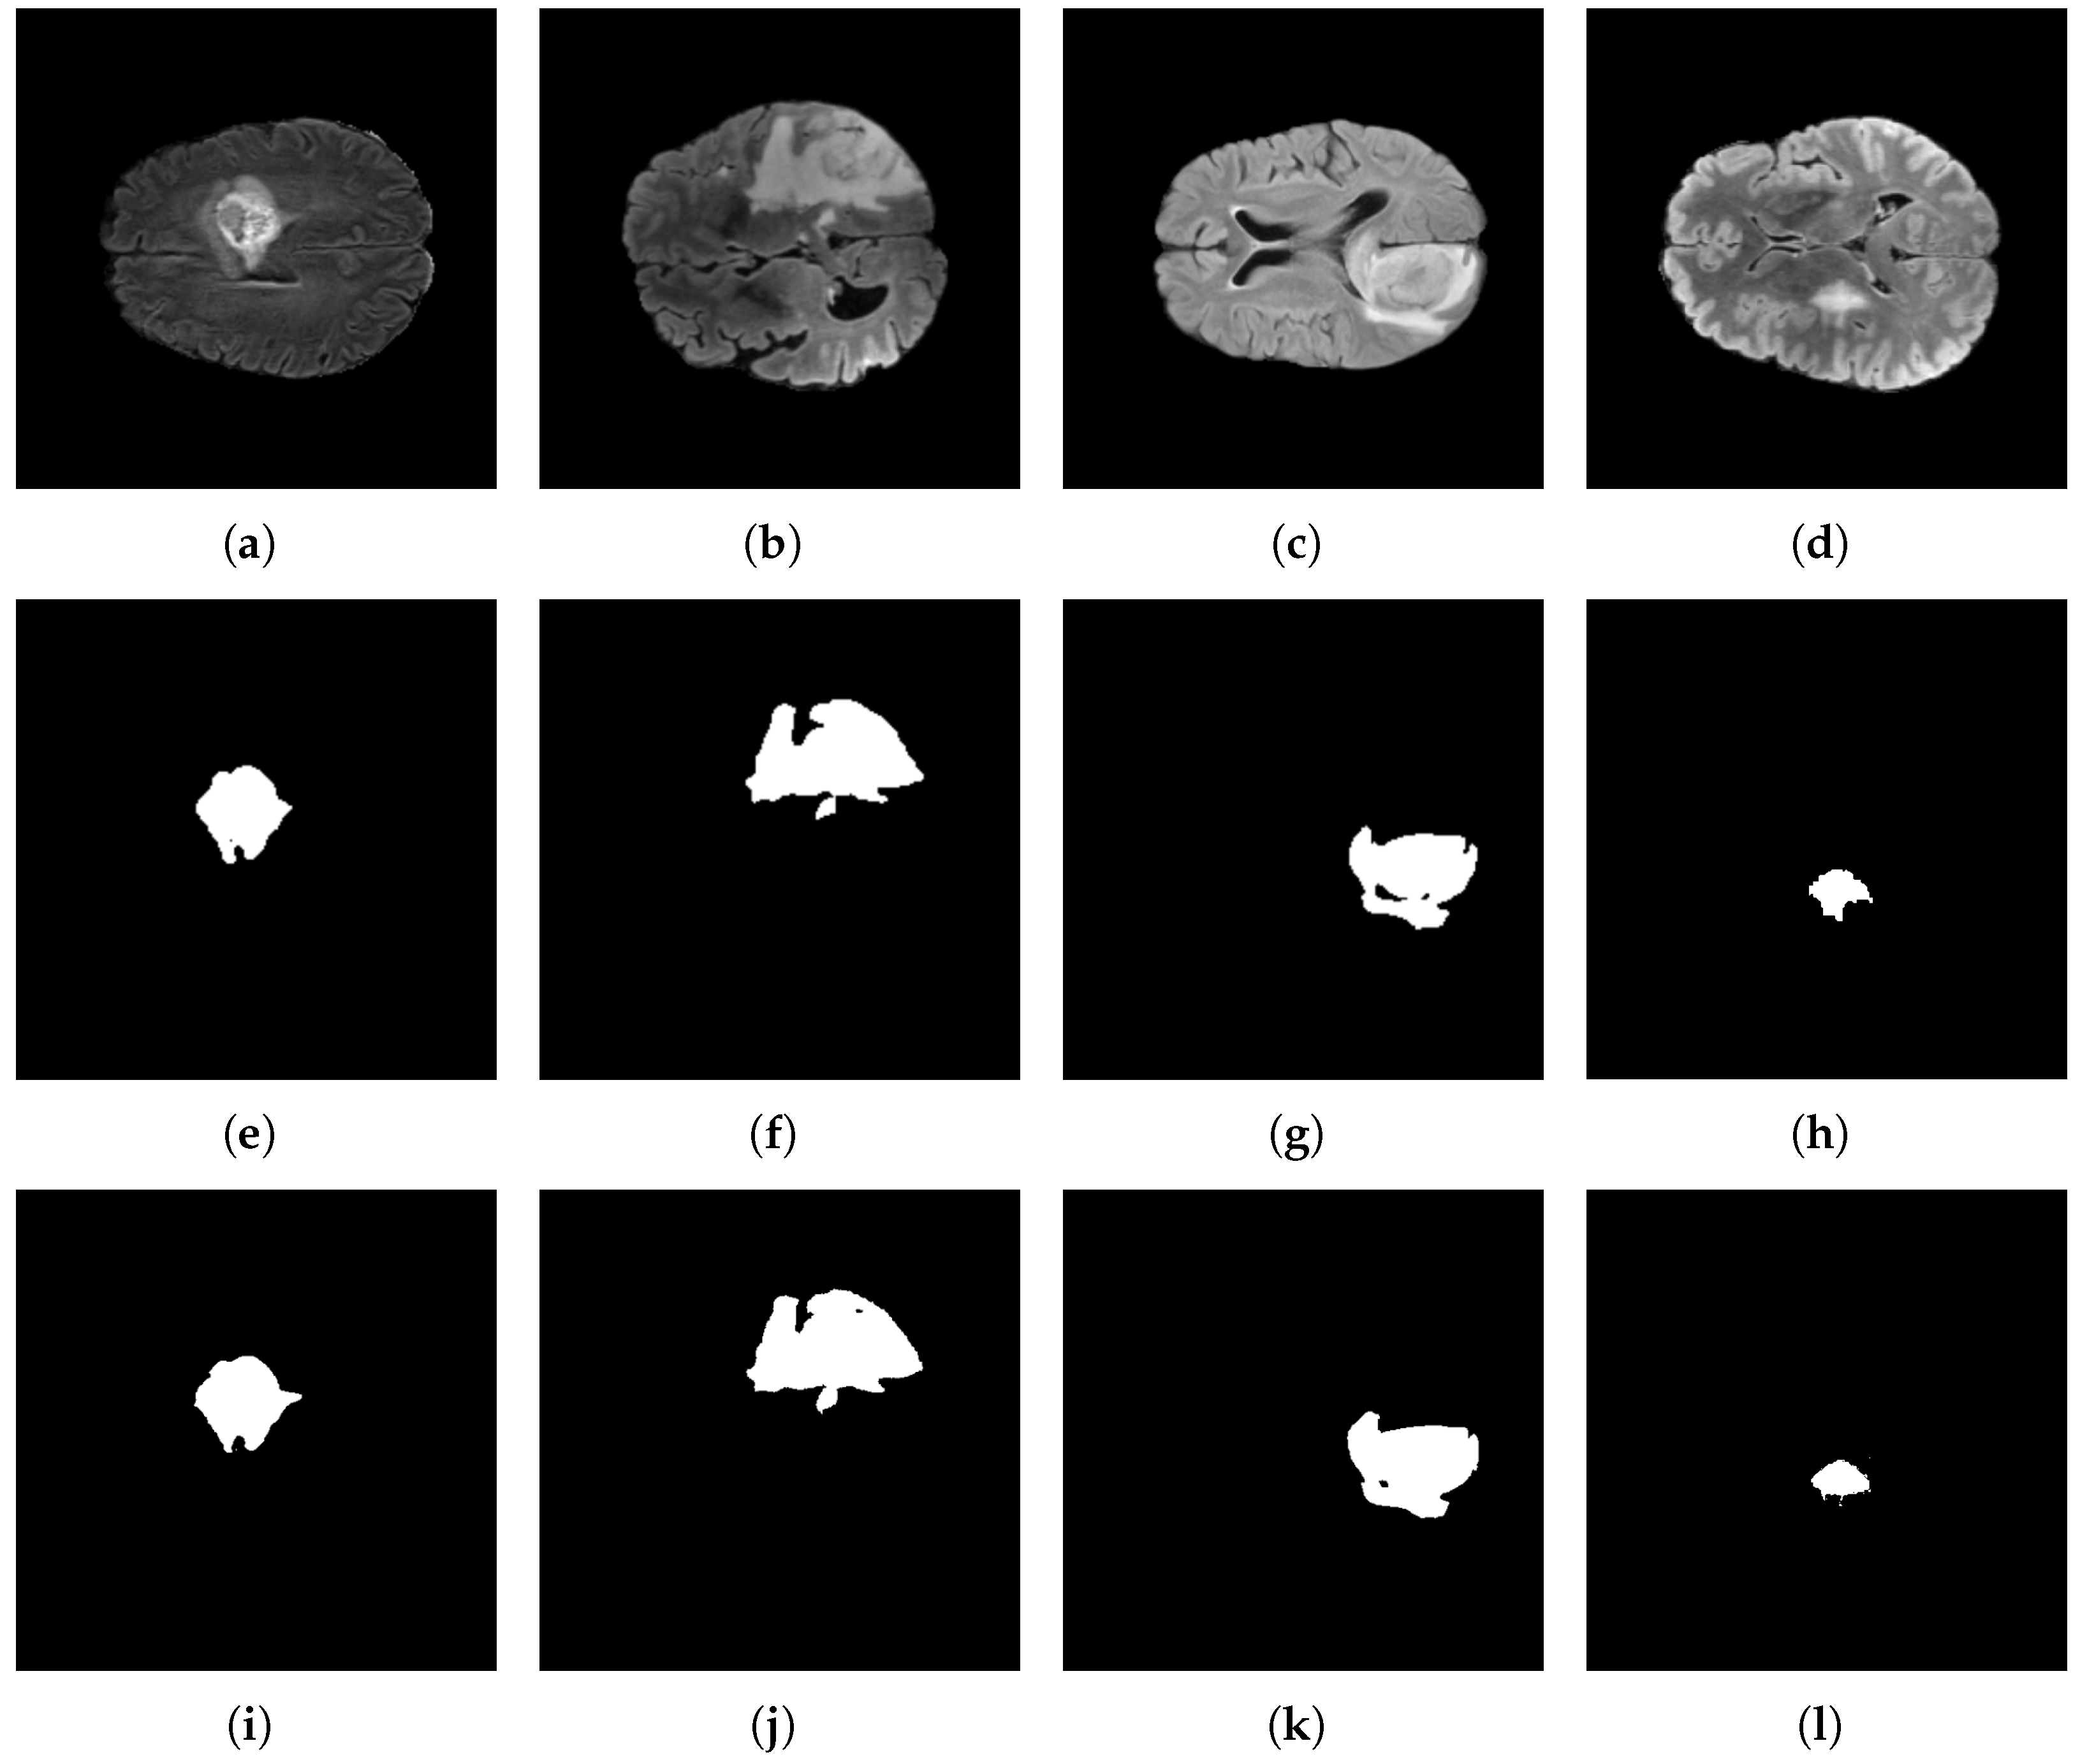

Figure 15 depicts the segmentation results for the BraTS 2021 dataset. The first row shows the original input images. The second row displays the corresponding ground-truth masks, while the third row illustrates the predictions generated by the proposed model.

Figure 15e shows a tumor with a rounded morphology; correspondingly, the model completely delineates it in Figure 15i, preserving a smooth boundary. By contrast, Figure 15f shows a spiculated contour with sharp protrusions, and the model accurately captures these border irregularities in Figure 15j without excessive smoothing effects. Finally, Figure 15h contains a small tumor; nevertheless, the model consistently localizes and segments it in Figure 15l, demonstrating sensitivity to small targets while limiting over-segmentation of adjacent tissues.

Figure 16 depicts the segmentation results for the BraTS 2023 dataset. The first row displays the original input images, the second row shows the corresponding ground-truth masks, and the third row illustrates the predictions generated by the proposed model. Figure 16e shows the ground-truth label, which exhibits an irregular morphology with a pronounced curvature; correspondingly, Figure 16i shows that the model accurately reproduces this complex boundary, yielding an essentially exact delineation.

Figure 16f depicts the ground-truth annotation of a lesion with irregular, spiculated margins; correspondingly, Figure 16j shows that the model faithfully reproduces these peak-like protrusions, preserving fine boundary detail without undue smoothing. Figure 16g depicts the ground-truth label of an irregular lesion that contains a small central region of normal-appearing tissue. Correspondingly, Figure 16k shows that the model not only recovers the overall lesion extent but also preserves this internal exclusion, refraining from labeling the central region as tumor despite its limited size. This behavior indicates precise boundary discrimination and a low propensity for over-segmentation. Furthermore, Figure 16h illustrates a comparatively small lesion. However, its limited extent poses a detection challenge; the model consistently localizes and segments the region in Figure 16l, demonstrating sensitivity to small targets.